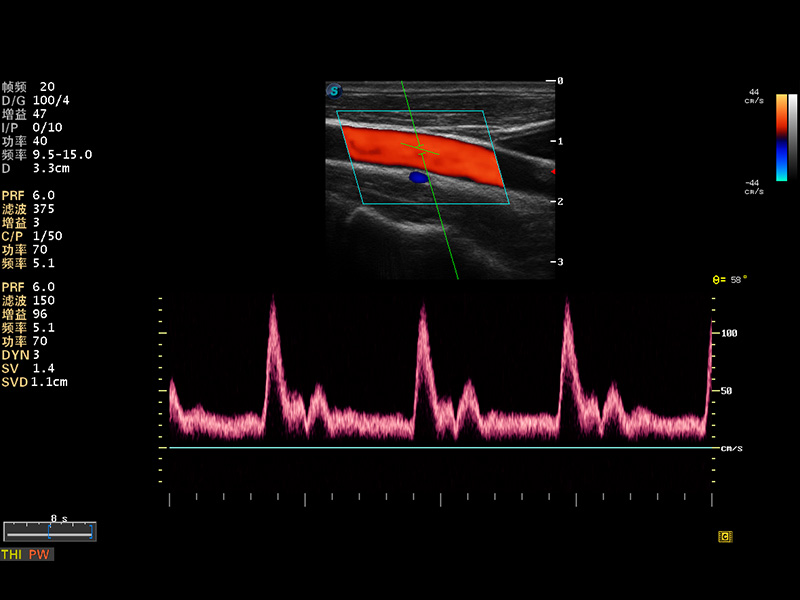

S8 EXP便携式彩色多普勒超声诊断仪是狗万官方网站研发的高端全身应用型便携彩超。高通道的VIS平台融合可视化(Visual)、智能化(Intelligent)和人性化(Smart)的特点,配以狗万官方网站自主研发生产的探头大家族,使您能够快速、准确的获得病人信息,提高工作效率的同时减轻疲劳。

μ-Scan微米成像